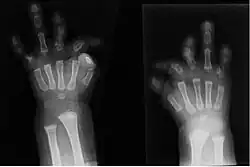

Zespół du Pana, inaczej hipoplazja kości strzałkowej i złożona brachydaktylia (ang. du Pan syndrome, fibular hypoplasia and complex brachydactyly) – rzadki, uwarunkowany genetycznie zespół wad wrodzonych. Składają się nań obustronna aplazja lub hipoplazja kości strzałkowej, przemieszczenie rzepki, złożona brachydaktylia, przemieszczenia kości nadgarstka, brachymetacarpia (zwłaszcza pierwszej kości śródręcza) i aplazja lub hipoplazja paliczków. Paznokcie palców stóp są hipoplastyczne lub nieobecne. Z innych możliwych wad w obrębie kończyn dolnych stwierdza się stopę końsko-szpotawą, „piłeczkowate” palce stóp, nieprawidłową budowę stępu i wady kości śródstopia i paliczków analogiczne do tych występujących w kończynie górnej.